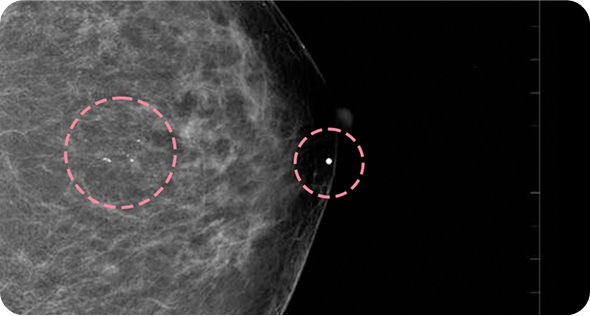

맘모톰시술 후 병리조직검사에서 상피내암(조기유방암)으로 진단되어 대학병원으로 연계해 드린 환자분의 사례입니다. 암을 초기 단계에 찾음으로써 항암치료 없이 간단한 수술을 통해 치료가 가능하였습니다.